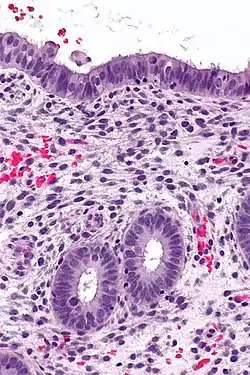

![]() Endometrium in the proliferative phase | |

The endometrium consists of a single layer of columnar epithelium plus the stroma on which it rests. The stroma is a layer of connective tissue that varies in thickness according to hormonal influences. In the uterus, simple tubular glands reach from the endometrial surface through to the base of the stroma, which also carries a rich blood supply provided by the spiral arteries. In a woman of reproductive age, two layers of endometrium can be distinguished. These two layers occur only in the endometrium lining the cavity of the uterus, and not in the lining of the Fallopian tubes.[3][4]